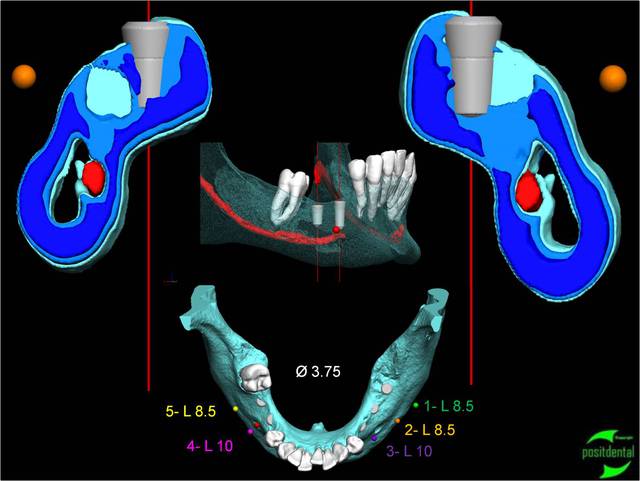

et là !

Image8 qjk3fn - Eugenol

pxav

30/04/2010 à 14h37

si le sujet c'est l'implant c'est correct, si c'est le guide c'est flou...

par contre bravo pas de sang sur les gants